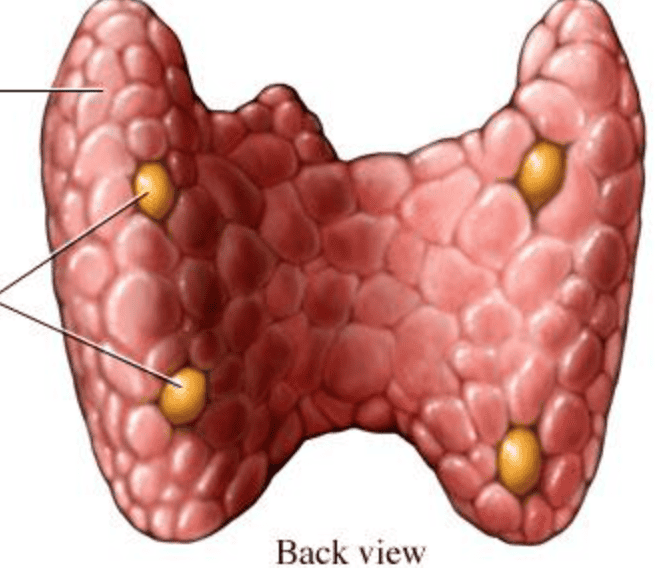

Parathyroid Glands-- yellow

Parathyroid